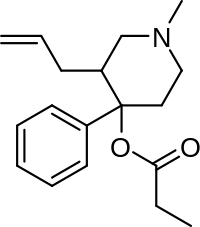

Phenylpiperidines

- Pethidine (meperidine)

- Ketobemidone

- MPPP

- Allylprodine

- Prodine

- PEPAP

- Promedol